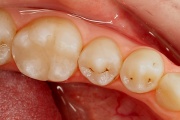

kaaries